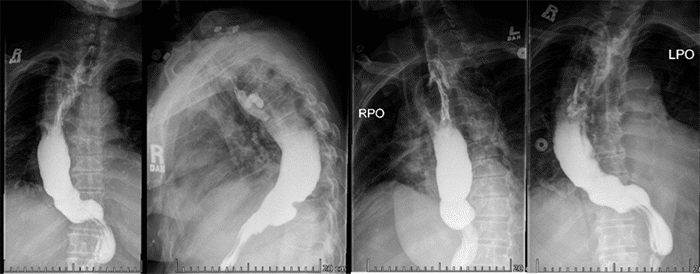

Postoperative evaluation included a single-contrast esophagram at four weeks, which revealed patent anastomosis in the upper mediastinum with no evidence of anastomotic leak or stricture (Figure 4). At eight months, end ileostomy was reversed without complications and remained free of esophageal cancer at 27 months follow-up. However, despite dietary and lifestyle modifications, the patient continues to suffer from moderate gastroesophageal reflux disease (GERD) with post-prandial abdominal colic with cramping and intermittent bouts of explosive diarrhea.

Figure 4. Four Weeks Post-MIE Esophagram Demonstrating Patent Esophagogastric Anastomosis Without Evidence of Leak or Stricture. Published with Permission